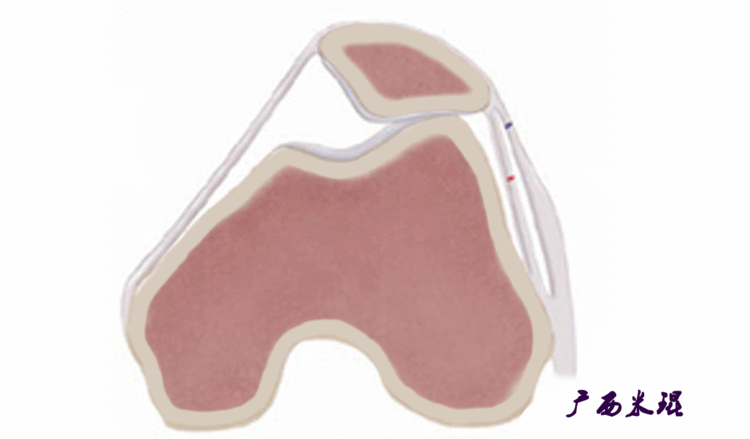

说到髌骨脱位,首先就要了解髌骨,髌骨是人体最大的籽骨,倒三角状位于膝关节前方,它的上缘与股四头肌腱相连,下缘通过髌韧带止于胫骨结节上,两侧为股四头肌扩张部,髌骨后方的凸面为光滑的关节面,与股骨下端内外髁之间的滑车凹面关节面形成关节。尽管股四头肌中的股直肌、股中间肌、股外侧肌的作用方向与髌韧带不在一条直线上,髌骨有向外突出的倾向,但因股内侧肌有向内上方牵拉作用力而使髌骨维持在正常位置。